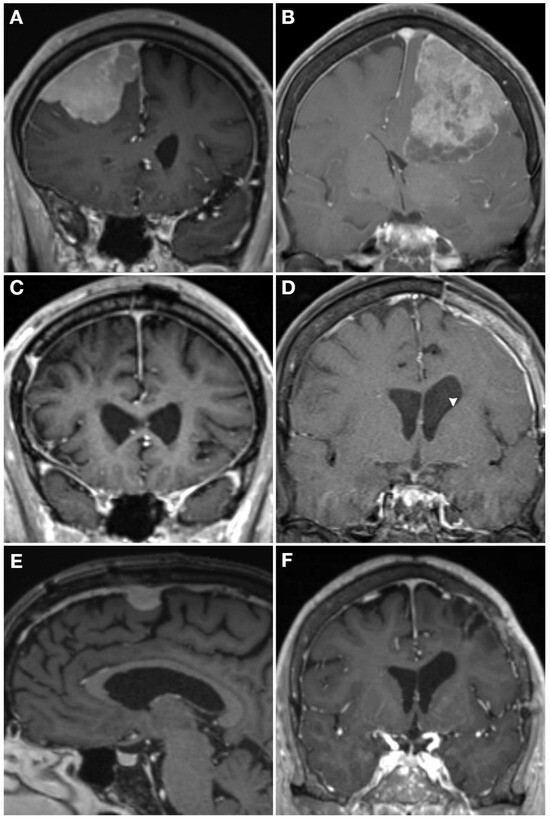

Typical Meningioma | Cohen Collection | Volumes | The。The Evolving Classification of Meningiomas: Integration of。Predicting Histologic Grade of Meningiomas Using a Combined。Meningiomas, Part II (Volume 170) (Handbook of Clinical Neurology, Volume 170) ハードカバー – 2020/8/14英語版 Michael W. McDermott MD (編集)※中古品のため、使用できれば良いという方のみのご購入をお待ちしております。角に少々イタミあり。中古品のため、多少のスレ、イタミ等ありますが、書き込みなく、とても良好な状態です。※商品状態の少々の見落としはご理解下さい。※値引交渉にはお答え致しません。※希少品の為、定価より高額の場合があります。※都合により発送方法を変更する場合があります。【佐川急便/日本郵便から佐川急便/日本郵便及びその逆等】※ビニールにて梱包し発送致しますが、保管、輸送によるイタミ等はご容赦下さい。※コメント不要、即購入にてご注文お願いします。。EANO guidelines for the diagnosis and treatment of。野口晴哉 口述 整体操法初等講座 全25冊。健康・医学専門雑誌コレクション。QB RB 2冊セット おまけ付き 看護師国家試験 2025年114回。【新品未使用】イヤーノート2026、内科専門医•総合内科専門医セット【バラ売可】。★8割復元!2024年度JBPOT復元。望診 自然療法 代替療法 医療 看護 大森英桜 日本CI協会 マクロビオティック。【裁断済み】メカニカル・リンク : オステオパシー・アプローチ。橋本

30321-7/asset/bac1e41f-5d79-4c4f-8340-cd7e5e8414a6/main.assets/gr2_lrg.jpg)